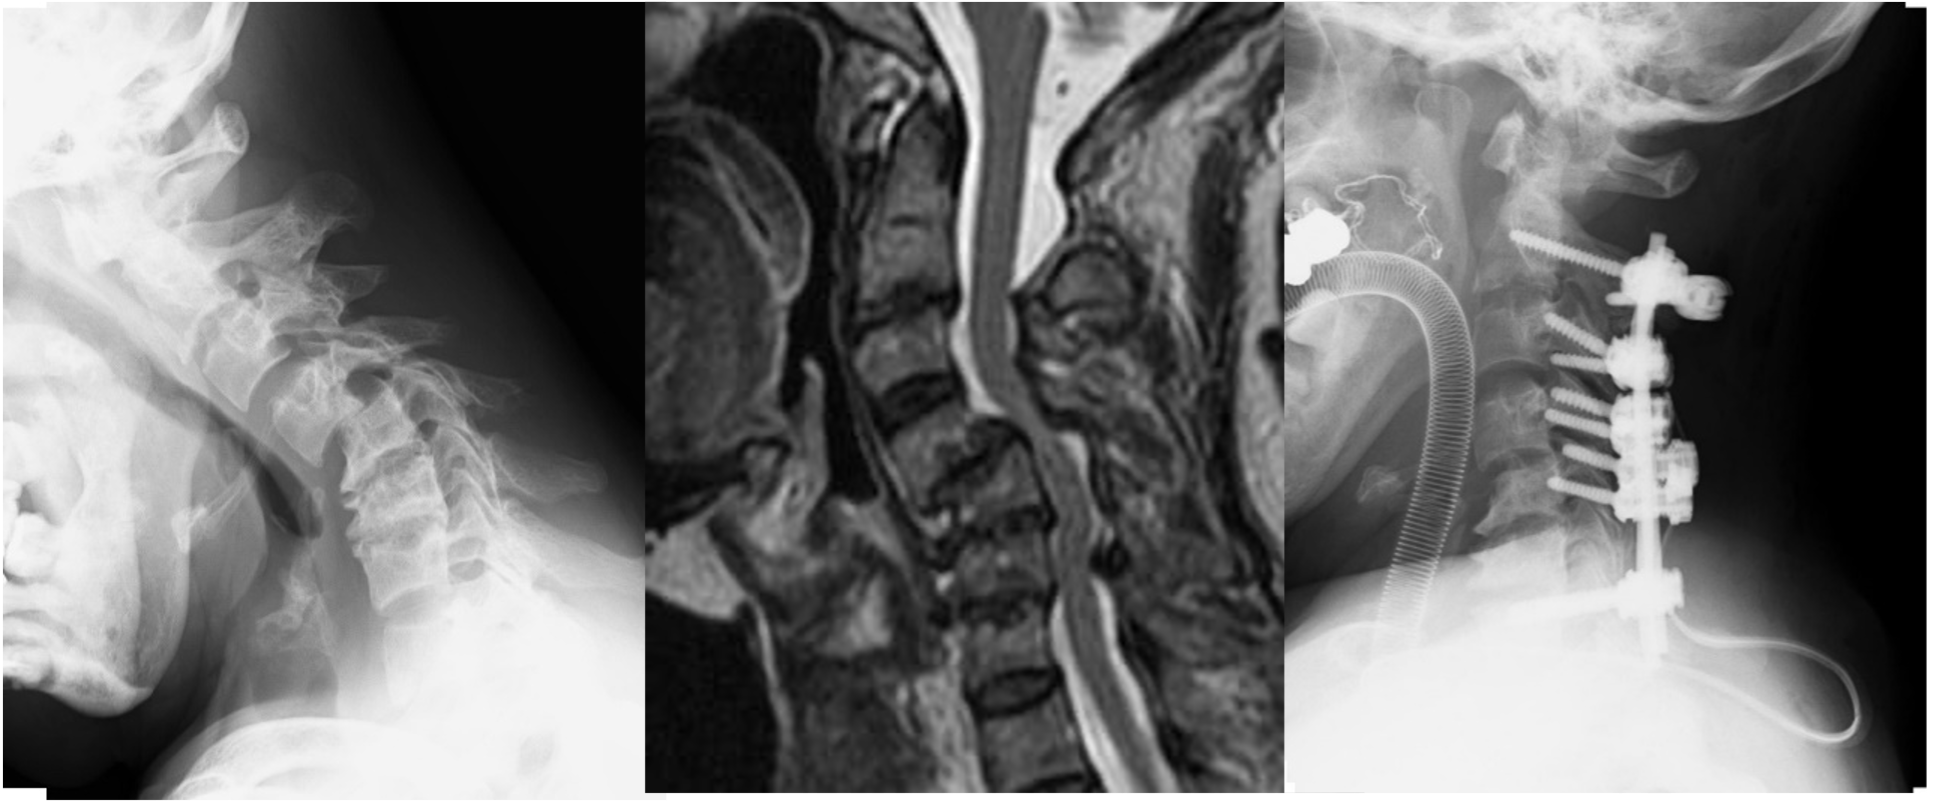

図(左)頚椎を横からみたX線。全体に椎間板がつぶれています。

(まん中、右)矢印の部分に偽腫瘍がみられ、脊髄を強く圧迫しています。

この患者様は頚椎後方固定術を受け、歩行困難で車椅子生活でしたが、術後3ヵ月で、自力杖歩行ができるまで回復しました。術後1年では、連続で20分の自力歩行が可能となりました。